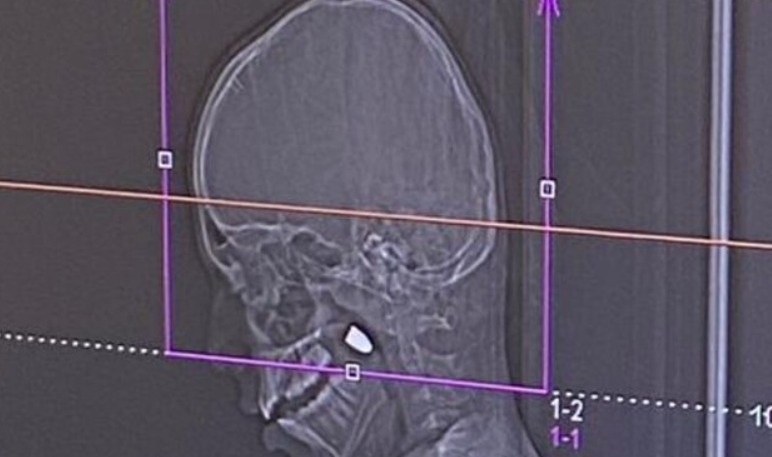

ברמב"ם בוצע ניתוח להוצאת קליע שפגע בראשו של ילד בן 11 תושב הכפר מר'אר, שעלה לגג ביתו לצפות בחגיגות כניסת ערב השנה האזרחית שכוללות, כמדי שנה, זיקוקים ואווירה שמחה. מייד עם רדתו מהגג, בני הבית שמו לב כי יורד לו דם מאזור הפנים. הילד פונה לטיפול רפואי במרכז הרפואי פוריה, שם, לאחר בדיקת סי-טי, התברר שהוא נפגע מקליע שננעץ בראשו מאחורי הלסת.

צילום רמב"ם

הילד הועבר למרכז הרפואי רמב"ם, ואושפז במחלקה לטיפול נמרץ ילדים, כשהוא בהכרה אך תחת השגחה צמודה. הוא עבר בהצלחה ניתוח מורכב להוצאת הקליע מראשו, על ידי צוותי המחלקה לפה ולסתות, כירורגית ילדים ונוירוכירורגית ילדים ברמב"ם.

לדברי ד"ר סאלח נסייר, רופא בכיר במחלקה לפה ולסתות ברמב"ם: "הכדור הצליח לחדור את אזור הגולגולת של הילד ונתקע באזור הפנים. הניתוח שבוצע בהרדמה כללית, עבר בצלחה, הקליע הוצא ללא סיבוכים נוירולוגיים וללא פגיעות משמעותיות". ד"ר נסייר הוסיף שמדובר בנס שכן הקליע שחדר לראשו של הילד עלול היה לגרום לפגיעה קשה במוחו.